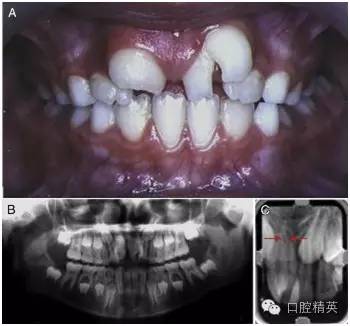

2002 年,一位左上中切牙巨大的 9 歲女孩因抱怨美觀問題而被轉(zhuǎn)診過來(圖 1)。經(jīng)初步檢查,患者口腔中剩余的其他乳牙與恒牙大小和形狀都表現(xiàn)正常,牙齒數(shù)量上無減少?;颊呒易迨放c既往病史不詳。

圖 1 左上巨牙癥術(shù)前資料。(A)口內(nèi)正面像。(B)x 線全景片。(C)根尖片,箭頭所指處表明兩顆牙齒的根管影像是分開的。

進(jìn)一步檢查發(fā)現(xiàn),一顆形狀不規(guī)則的多生牙與左上中切牙在冠部頸 1/3 處融合在了一起。然而,通過全景片與根尖片可以判斷出兩顆牙的根管影像是各自分開的 (圖 1-B,1-C[ 箭頭處])。這可以被認(rèn)為是一條垂直向的發(fā)育溝把牙冠從近中 1/3 處分成兩個(gè)錐形牙冠造成的并生。患牙牙冠近遠(yuǎn)中總寬度為 15mm,而正常的右上中切牙牙冠近遠(yuǎn)中寬度只有 10mm。

由此造成的切牙區(qū)域的擁擠導(dǎo)致了融合牙遠(yuǎn)中部分的唇傾(作為整體來描述則是遠(yuǎn)中頰側(cè)扭轉(zhuǎn))。對(duì)融合牙用冷測(cè)法進(jìn)行牙髓溫度測(cè)試,測(cè)試結(jié)果為正常。

根據(jù) x 線片,可以清楚地觀察到兩個(gè)明顯的牙根因融合的牙骨質(zhì)連在了一起。結(jié)合口內(nèi)臨床檢查可以確定,這是由一顆不規(guī)則的多生牙與左上中切牙融合在一起的融合牙。檢查過程中,未發(fā)現(xiàn)牙髓與根尖周組織存在其他的異常。